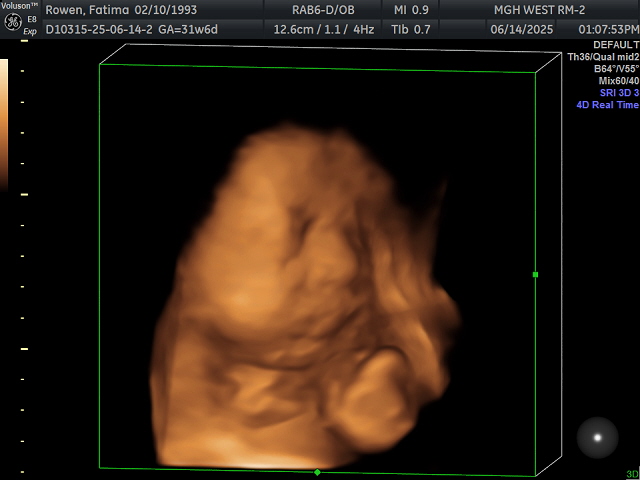

I was able to see his chubby cheeks and cute lips. I saw him yawn and play with his foot by grabbing it. It’s so reassuring to see that he’s doing well inside me. It helps during those rough moments—like throwing up or dealing with heartburn—when I picture his cute face in my head. It helps me push through the sleepless nights. We also saw him moving around, which explains a lot of what I’ve been feeling in my belly.

Like every single ultrasound, no matter how much I moved around, his face was really hard to capture. He always smushes his face against the placenta, and I guess he’s just super comfy there haha. At least I got a little peek at his chubby face though. At the end of the session, since Katya loved the unicorn plushie, we decided to put his heartbeat sound inside the unicorn as a keepsake. Katya seems to half understand that it’s her little brother’s heartbeat now. She occasionally hugs it and tells me it’s her brother, which is so sweet. I cannot wait for Katya to meet him in August!